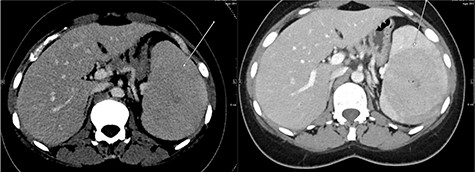

Abdominal ultrasonography showed a 5.0 × 5.0 cm well-defined, rounded, lobulated and hypoechoic vascular solid splenic lesion with no increased transmission or calcification. This lesion had vessels radiating from the center to the periphery (Fig. 1). Further evaluation with contrast-enhanced computed tomography (CT) of the abdomen showed a 6.0 × 5.6 × 4.4 cm solitary, rounded and lobulated non-calcified mass in the spleen, demonstrating heterogeneous, linear and nodular arterial enhancement with progressive filling in the portal venous and delayed phases (Fig. 2).

Top image shows abdominal CT scan arterial phase axial section with a hypodense, solitary, rounded and lobulated non-calcified mass lesion in spleen. Bottom right and left images show abdominal CT scan portovenous and delayed phase axial images showing a hypodense lesion and areas of filling (arrows in both images) which becomes mostly isodense to spleen; incidental finding of a splenic cyst.